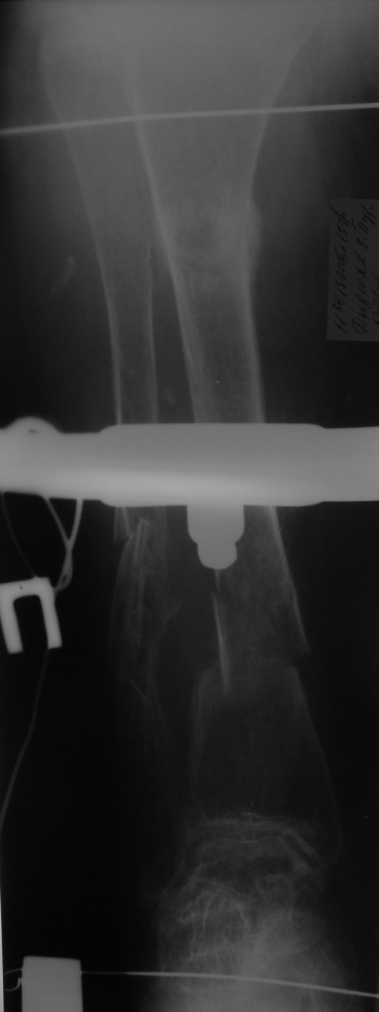

А что доступно на месте? У нас бы голени зашифтовали закрыто стержнями диаметром 12 мм с запирающими винтами 6 мм производства предприятия "ЦИТО", Москва.

Если при введении стержня будет видно, что из-за искривления дело идет к перфорации стенки, надо будет сделать чрескожную остеотомию на уровне кончика стержня.

Во-1-х, интрамедулярный остеосинтез относится к методам, дающим относительную, не абсолютную стабильность. Во-2-х, стабильность неплохо обеспечивается запирающими винтами. В-3-х, несоответствие кривизны стержня и канала приводит к повышению стабильности, в-4-х, канал можно искусственно сузить введением отклоняющих (трансмедуллярных, Poller) винтов.